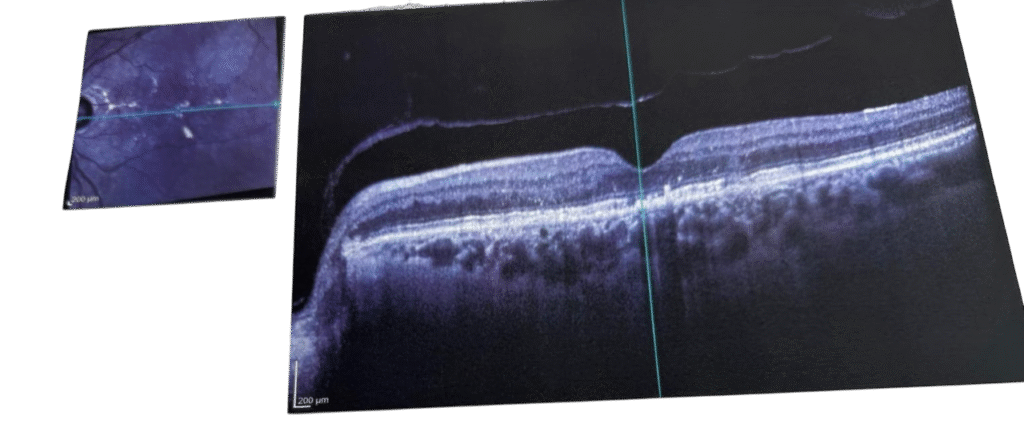

Resim 1: Sarı nokta hastalığı tedavi öncesi

YAŞ TİP SARI NOKTA HASTALIĞI

Görme noktasının altında olmaması gereken yeni bir zar gelişir. Damarsal yapısı çok yüksek olan bu zar; foveanın (sarı nokta) altına sıvı ve kan sızıntısına sebep olur . Retinanın içinde sıvı birikmesi merkezi görmeyi bozar. Bu yapıyı söndürmek için göz içinde damar oluşumunu sağlayan faktörleri yok eden maddeleri içeren enjeksiyonlar yapılmalıdır. Tedavi protokolü standarttır. Başlangıçta yükleme dozu olarak 1 er ay arayla 3 defa enjeksiyon yapılır, daha sonra hastalığın gösterdiği gelişme göre hastalar ayda bir ya da daha geniş aralıklarla kontrol edilir. Aktivasyon varsa enjeksiyonlara devam edilir. Göz sakin bulunursa o seans atlanır. Enjeksiyonların ucu açıktır ve kaç enjeksiyon gerekiyorsa mutlaka yapması gerekir.